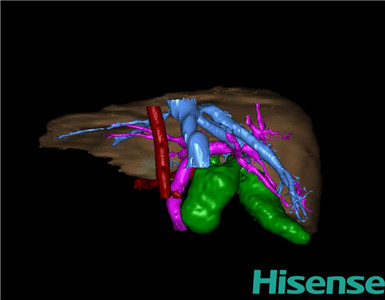

CT结果输入海信CAS系统后行3D重建及手术规划后,于2015-11-18全麻下行“胆总管囊肿切除+胆囊切除+胆总管-空肠吻合术”手术治疗:

将0.625mm双源薄层CT资料的静脉期和动脉期Dicom格式文件导入海信CAS系统。

通过调节窗宽窗位调整CT序号,对肝实质,胆囊,胆总管,下腔静脉,肝动脉、门静脉及肝静脉等进行三维重建;系统自动计算肝脏体积。

术前手术方案的规划。

术前三维重建:

重建图片